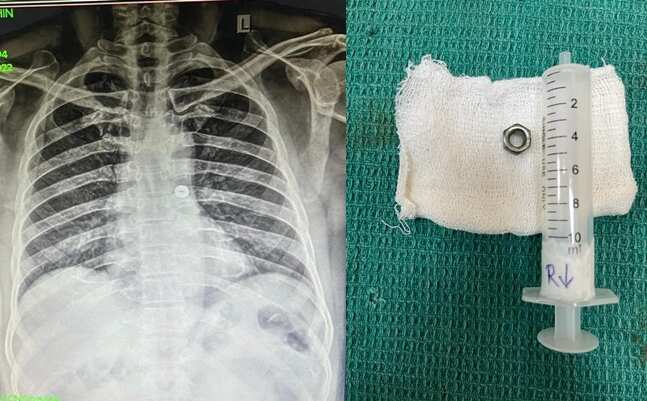

தவறுதலாக போல்ட் நட்டை விழுங்கிய எலக்ட்ரீசியன்... அறுவை சிகிச்சை மூலம் அகற்றிய கோவை அரசு மருத்துவர்கள்! 🕑 Fri, 21 Oct 2022

தவறுதலாக போல்ட் நட்டை விழுங்கிய எலக்ட்ரீசியன்... அறுவை சிகிச்சை மூலம் அகற்றிய கோவை அரசு மருத்துவர்கள்!